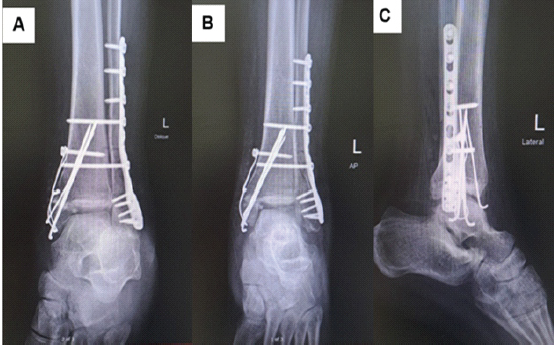

Post-operative management included pain control, regular wound care, dressing changes every 72 h, a 5-day course of antibiotics due to compromised local tissue conditions around the ankle, and non-weight-bearing mobilization. A post-operative X-ray confirmed proper alignment of the ankle joint and internal fixation of the fibula and medial malleolus (Fig. 5). A CT scan revealed proper alignment of the syndesmotic joint (red arrow) (Fig. 6).

Figure 5: Post-operative oblique (a), anteroposterior (b), and lateral (c) X-rays showing dual syndesmotic screw fixation and confirming restored ankle joint.